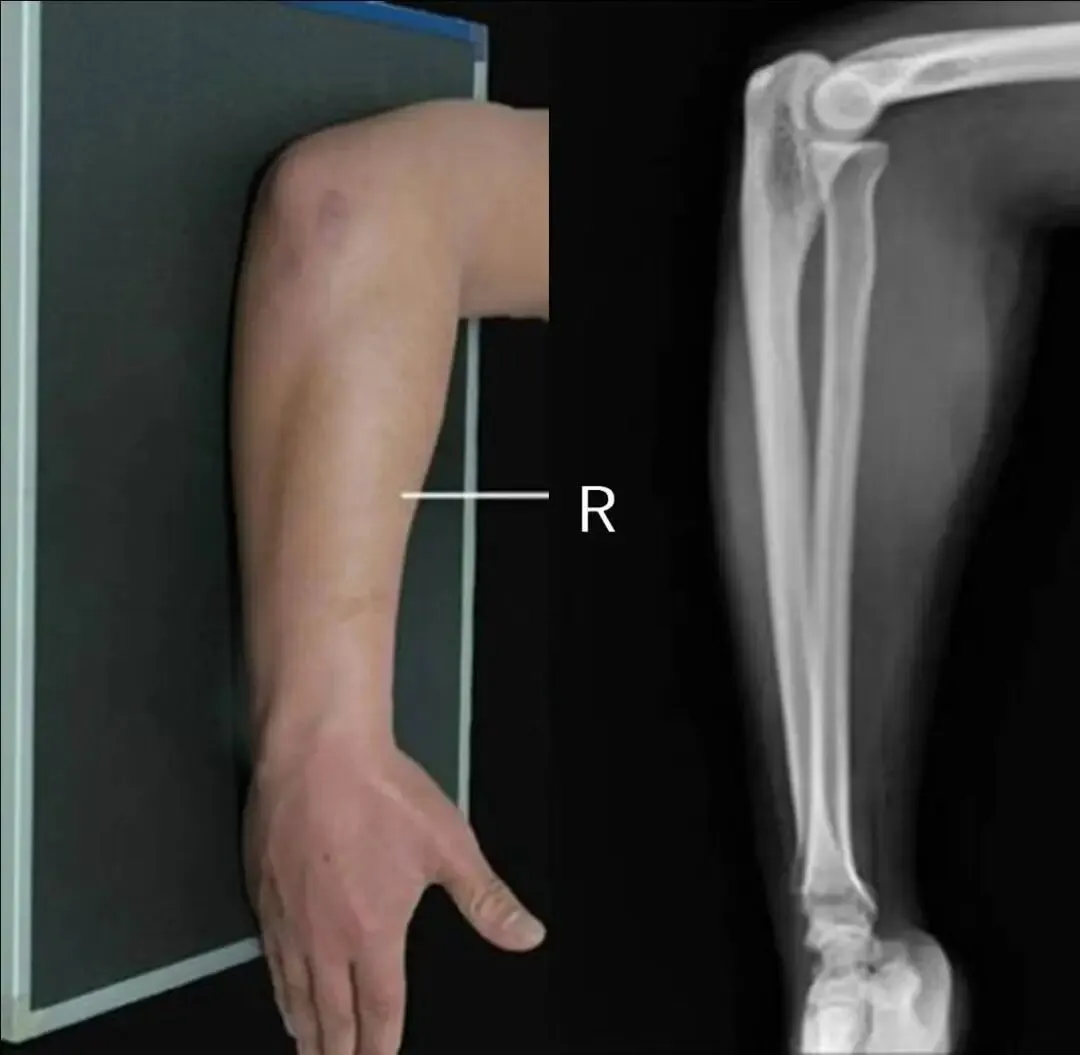

六、为何尺桡骨正位需伸直肘部拍摄,而侧位则弯曲肘部90°拍摄(仿如肘关节正侧位)?

八、为何桡尺骨正位需伸直肘部拍摄,而侧位则弯曲肘部90°拍摄(仿如肘关节正侧位)?

一、难道桡尺骨正侧位就必须全部伸直肘部或者全部弯曲肘部90°拍摄?说到底还是因为这样拍摄是标准的,有利于诊断。

三、假如说病人是靠近腕关节那一侧的桡尺骨有问题时,我们拍摄桡尺骨正侧位也只包括一侧腕关节时,这样的拍摄方法(全部伸直或者全部弯曲)也许不会发现此问题。但是病人是肘关节那一侧的桡尺骨有问题时,我们拍摄桡尺骨必须要包括肘关节时,这样的拍摄方法(全部伸直或者全部弯曲)就有问题啦!桡尺骨侧位片伸直显示不出肘关节侧位,桡尺骨正位片弯曲90°显示不出肘关节正位,我们都没法查看肘关节的解剖细节!

3.在一些特殊检查时,可能会出现影像技术的最终目标与技术标准发生冲突或不能兼容的情况。这时,应当视患者实际情况向标准靠近,但是却不能掩盖患者的伤情、病情和畸形状态,不能违背影像检查的最终目标。

4.对一些特殊病人、特殊体位处理的基本理念,在实际工作中应酌情考量而为......